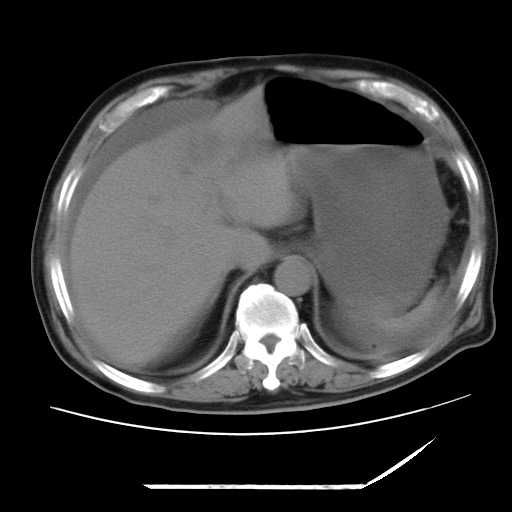

以下是引用zxl51642在2009-8-12 18:55:00的发言:[br]1、肠系膜脂肪浑浊,密度增高,腹水,支持腹膜炎诊断;2、右肾盂及输尿管中段结石,左输尿管起始段结石;3、胆囊切除术后改变?4、双侧胸膜腔少量积液;5、胰腺体积不大,勾勒清楚,肾前筋膜无增厚,不支持胰腺炎,请结合血尿淀粉酶及临床。